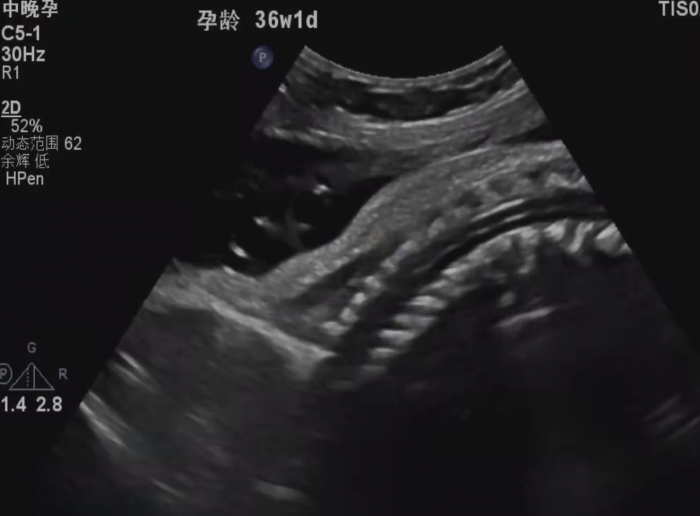

近日,在湖南长沙,一名孕期36周的准妈妈被发现胎位不正,肚子里的宝宝头朝上,屁股朝下。经过评估,湖南妇女儿童医院的郑岚琳主任医师隔着妈妈的肚皮,来了一招“乾坤大挪移”——臀位外倒转术。不到1分钟,医生就让宝宝掉了个头,顺利头朝下、屁股朝上,胎位瞬间转成头位。